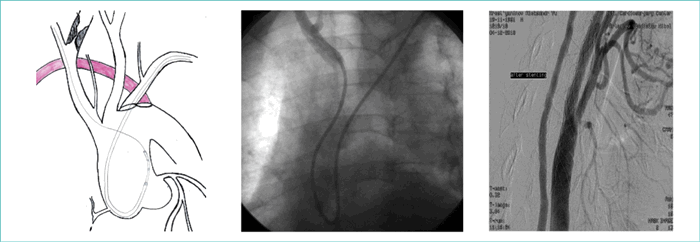

Принимая во внимание значительные трудности катетеризации правой общей сонной артерии через a. l., мы решили катетеризировать левую лучевую артерию дистально. Для достижения надежной поддержки направляющего катетера выбрали Claret-технику. Для этого безинтродьюсерный направляющий катетер JR 7.5F (ASAHI) был перемоделирован в Simmons- катетер. Для облегчения селективной катетеризации правой общей сонной артерии мы использовали в качестве удлинителя диагностический катетер Pigtail 5F (прием «Мать и дитя») (рис. 3).

Рисунок 3. Демонстрация технических решений для реализации первого этапа лечения

Figure 3. Technical solutions for the implementation of the first stage of treatment

Благодаря представленной стратегии удалось успешно закатетеризировать правую общую сонную артерию, свободно провести через направляющий катетер во внутреннюю сонную артерию все необходимые инструменты (устройство для профилактики эмболии Spider 6 мм ev3, стент Casper 9-30, баллонный катетер для постдилатации 5-20) и выполнить вмешательство с хорошим непосредственным ангиографическим результатом (рис. 4).

Рисунок 4. Ангиографический результат первого этапа лечения

Figure 4. Angiographic result of the first stage of treatment